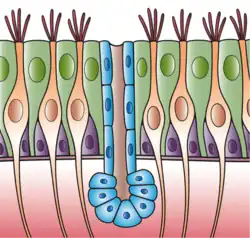

Illustration depicting the respiratory epithelium. Basal cells labelled as stem cells. | |

Respiratory epithelium, or airway epithelium,[1] is ciliated pseudostratified columnar epithelium a type of columnar epithelium found lining most of the respiratory tract as respiratory mucosa,[2] where it serves to moisten and protect the airways. It is not present in the vocal cords of the larynx, or the oropharynx and laryngopharynx, where instead the epithelium is stratified squamous.[3] It also functions as a barrier to potential pathogens and foreign particles, preventing infection and tissue injury by the secretion of mucus and the action of mucociliary clearance.

Structure

The respiratory epithelium lining the upper respiratory airways is classified as ciliated pseudostratified columnar epithelium.[4] This designation is due to the arrangement of the multiple cell types composing the respiratory epithelium. While all cells make contact with the basement membrane and are, therefore, a single layer of cells, their nuclei are not aligned in the same plane. Hence, it appears as though several layers of cells are present and the epithelium is called pseudostratified (falsely layered). The respiratory mucosa transitions to simple ciliated cuboidal epithelium and finally to simple squamous epithelium in the alveolar ducts and alveoli.[5]

Cells

The cells in the respiratory epithelium are of five main types: a) ciliated cells, b) goblet cells, c) brush cells, d) airway basal cells, and e) small granule cells (NDES)[6] Goblet cells become increasingly fewer further down the respiratory tree until they are absent in the terminal bronchioles; club cells take over their role to some extent here.[7] Another important cell type is the pulmonary neuroendocrine cell. These are innervated cells that only make up around 0.5% of the respiratory epithelial cells.[7] The ciliated cells are columnar epithelial cells with specialized ciliary modifications. The ciliated cells make up between 50 and 80 per cent of the epithelium.[8]

The basal cells are small, nearly cuboidal that differentiate into the other cell types found within the epithelium. Basal cells respond to injury of the airway epithelium, migrating to cover a site denuded of differentiated epithelial cells, and subsequently differentiating to restore a healthy epithelial cell layer. The differentiated epithelial cells can also dedifferentiate into stem cells and contribute to the repairing of the barrier.[15]